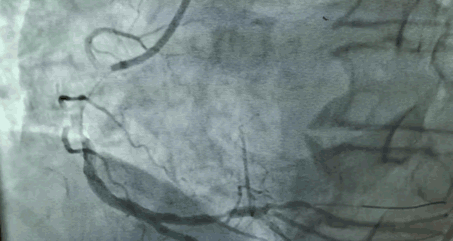

第一个病人的特点是,需要在解决主动脉瓣问题的同时,解决冠状动脉的问题。针对病人特点,来永强教授和周玉杰教授提前在网上进行了会诊,设计一站式杂交手术,前降支和右冠各放一个支架,同时用SAPIEN 3瓣膜进行TAVR手术。

“相当于经皮主动脉瓣膜植入术中同时行PCI手术,不开胸,对患者来说是获得最大的效益。”周玉杰教授表示,TAVR同期行PCI,这两个手术合在一起,带来了病人的双获益。